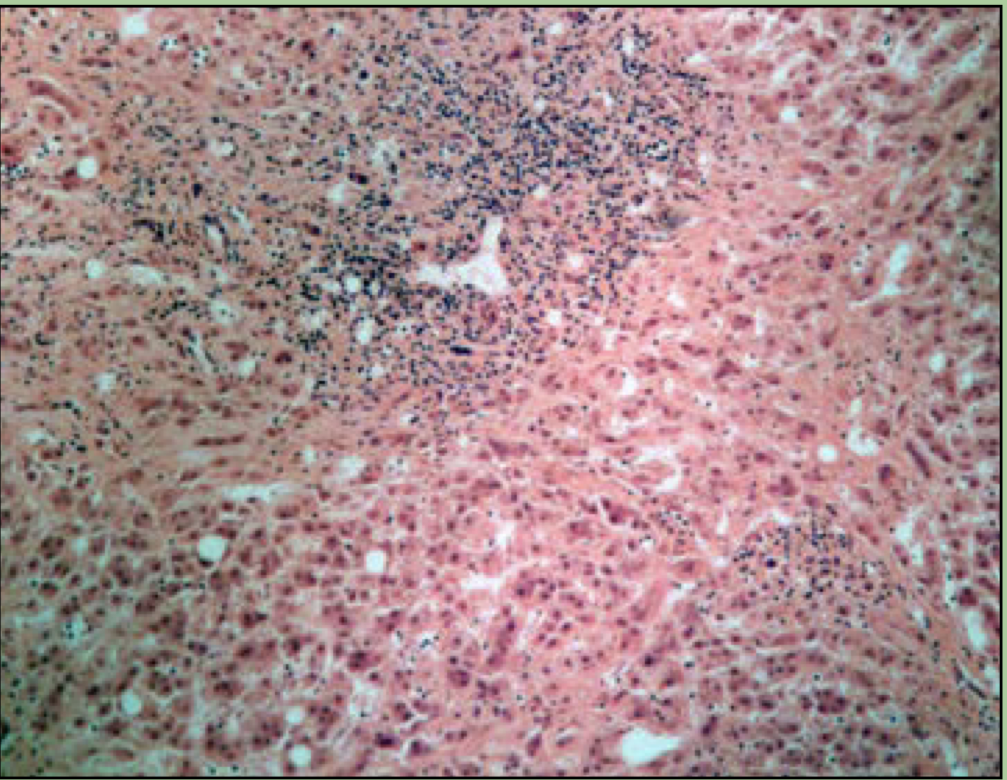

New cards

what disease is this?

Hodgkins granuloma - cancer of lymphatic system. can lead to breakdown of splenic pulps

Reed-Sternberg cells

76

What disorder is this?

Cirrhosis

fibrous fatty deposits in liver

87

Hepatitis

viral infection of the liver